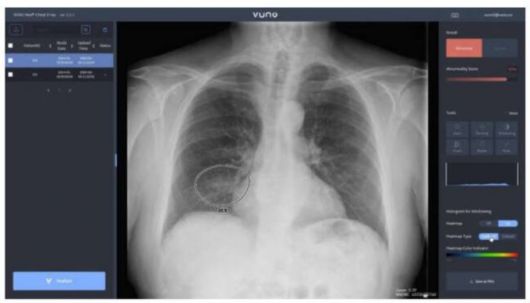

뷰노의 AI기반 엑스선 판독시스템/사진=뷰노 |

이에앞서 코로나19 진원지인 우한 시내 중난병원 등 34개 의료기관은 중국 현지 스타트업 인퍼비전이 개발한 AI기반 CT 판독 프로그램으로 3만2000건의 의심환자를 발견했다. 국내에서도 뷰노와 JLK인스팩션 등 의료 IT기업들이 확진자의 흉부 X레이 영상을 AI로 수초내로 판독해 중증환자를 분류하는 기술을 각각 홍천군과 대구지역 등 지역병원들에 제공하고 있다.